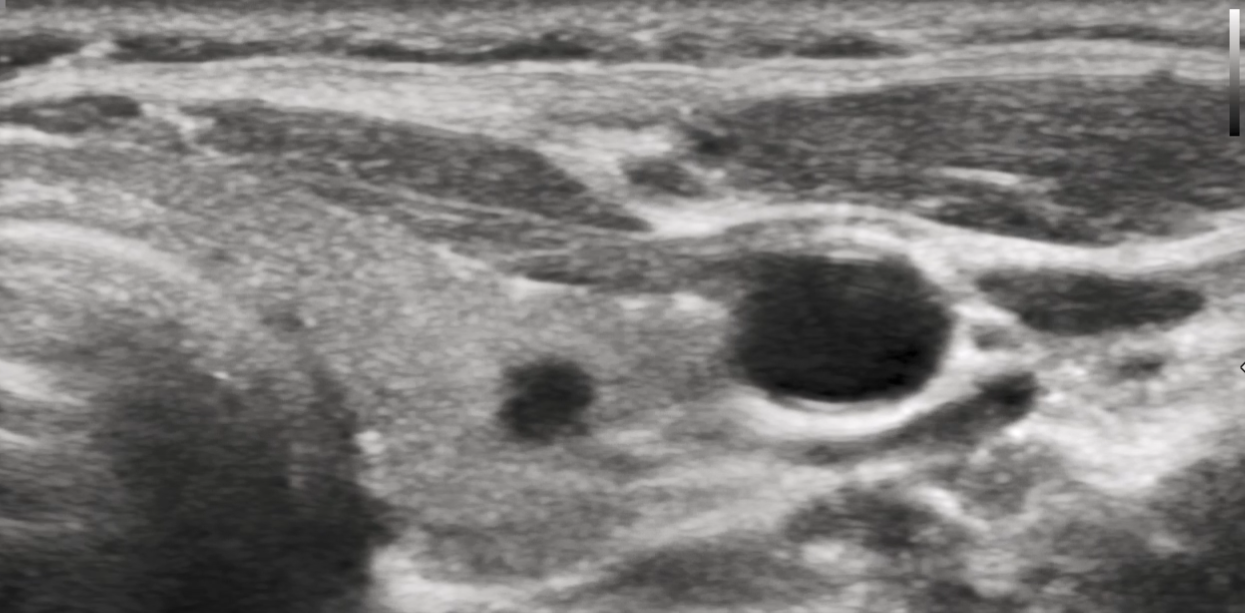

一、什么是甲狀腺濾泡性腫瘤?甲狀腺濾泡型腫瘤是常見的一種甲狀腺腫瘤,而不是普通良性的甲狀腺結(jié)節(jié),其特點(diǎn)是會(huì)持續(xù)增長和惡變,主要分為良性的濾泡腺瘤和惡性的濾泡癌(占比10-15%),濾泡癌可分為微小浸潤型及廣泛浸潤型兩種亞型,其惡性風(fēng)險(xiǎn)較高,易發(fā)生骨及肺的遠(yuǎn)處轉(zhuǎn)移,嚴(yán)重程度高于最常見的甲狀腺乳頭狀癌。二、如何診斷甲狀腺濾泡性腫瘤?甲狀腺結(jié)節(jié)的良/惡性診斷,通常依靠B超和細(xì)針穿刺病理來鑒別,而病理最為關(guān)鍵。但是甲狀腺濾泡性腫瘤的診斷,目前主要依據(jù)B超,典型的超聲表現(xiàn)有:1.?類圓或者橢圓形2.?實(shí)質(zhì)性低回聲或者等回聲3.?有聲暈(包膜)4.?環(huán)形血流信號(hào)三、為何穿刺細(xì)胞學(xué)無法診斷和鑒別濾泡性腫瘤?穿刺細(xì)胞學(xué)病理檢查,良性的濾泡腺瘤和惡性的濾泡癌均表現(xiàn)為濾泡上皮增生,兩者并無差異,無法鑒別。根據(jù)美國國家癌癥研究院甲狀腺細(xì)胞病理報(bào)告系統(tǒng),濾泡性腫瘤或疑似濾泡性腫瘤,一般穿刺病理報(bào)告為BethesdaⅣ類,惡性風(fēng)險(xiǎn)為15%~30%,?通常建議行腺葉切除術(shù)。只有手術(shù)醫(yī)生把甲狀腺病變切除后,病理醫(yī)生在顯微鏡下仔細(xì)觀察每個(gè)腫瘤切片的包膜,是否存在血管和包膜侵犯,才能判斷究竟是良性還是惡性,由于過程復(fù)雜、工作量較大,通常需要三個(gè)工作日。而甲狀腺乳頭狀癌,只要穿刺細(xì)胞學(xué)檢查發(fā)現(xiàn)典型異常特征(核大、核溝、包涵體等),就可以診斷。四、甲狀腺濾泡性腫瘤如何治療?由于細(xì)針穿刺細(xì)胞病理學(xué)檢查,無法鑒別甲狀腺濾泡性腫瘤的良性還是惡性,因此超聲診斷為甲狀腺濾泡性腫瘤者,甲狀腺外科治療規(guī)范為手術(shù)切除病變所在的單側(cè)甲狀腺,不建議消融治療,因?yàn)闉V泡性腫瘤一般較大,很難消融徹底,就算良性后期也會(huì)快速增長。如果是惡性,更延誤了治療,等發(fā)現(xiàn)肺部、骨骼轉(zhuǎn)移才治療為時(shí)已晚。臨床上診斷為甲狀腺濾泡性腫瘤者,手術(shù)切除后常見的病理有三種結(jié)果,對(duì)應(yīng)的處理方式如下:1.?術(shù)后病理良性的濾泡腺瘤:無需處理。2.?術(shù)后病理微小浸潤型濾泡癌,服用左甲狀腺素片抑制腫瘤復(fù)發(fā),定期復(fù)查。3.?術(shù)后病理廣泛浸潤型濾泡癌,再次手術(shù)切除剩余的對(duì)側(cè)甲狀腺,放射碘治療,服用左甲狀腺素片抑制腫瘤復(fù)發(fā),定期復(fù)查。五、基因檢測(cè)的意義RAS基因突變和(或)PAX8對(duì)診斷甲狀腺濾泡性腫瘤有一定價(jià)值,但是準(zhǔn)確性不高,臨床并未推廣使用,六、甲狀腺濾泡癌的預(yù)后微小浸潤型濾泡癌預(yù)后相對(duì)較好,若手術(shù)時(shí)腫瘤直徑<4cm、年齡在45歲以下并且未發(fā)生轉(zhuǎn)移,一般問題不大。但是廣泛浸潤型濾泡癌的預(yù)后,類似于低分化癌,若手術(shù)診斷時(shí)已經(jīng)出現(xiàn)遠(yuǎn)處轉(zhuǎn)移,預(yù)后較差。